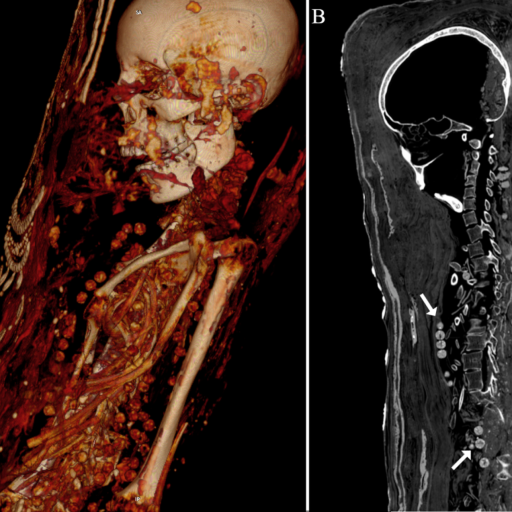

Genetic changes in Egypt might have been caused by trade routes.